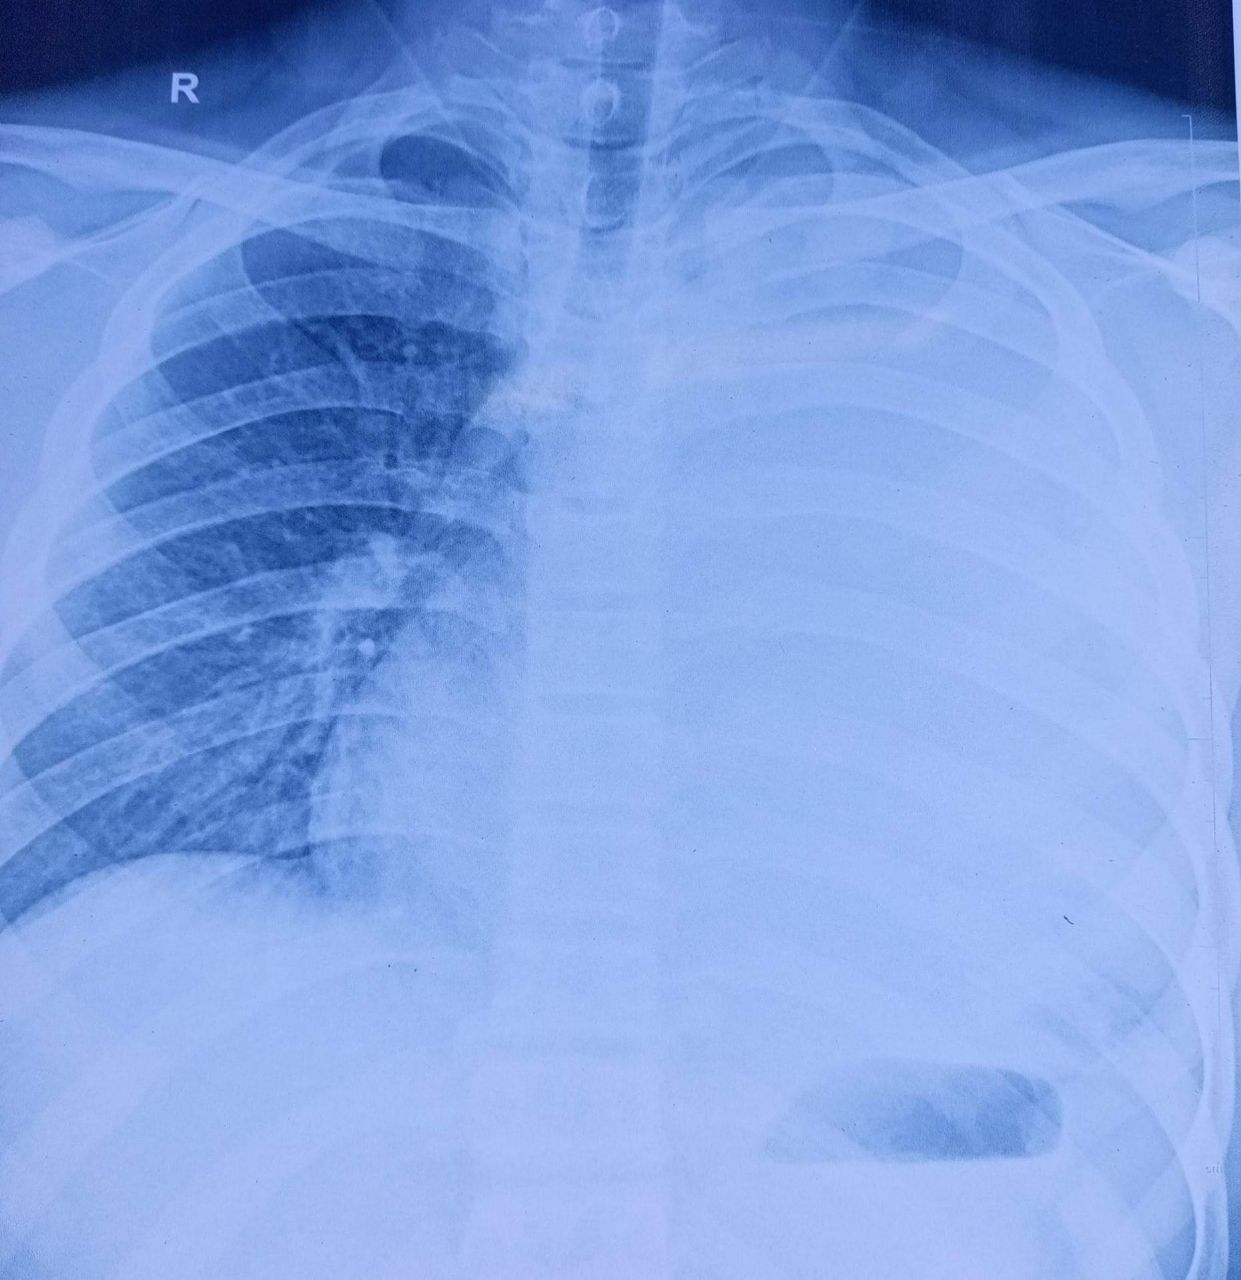

MENGENAL BRONKOPNEUMONIA

𝗠𝗘𝗡𝗚𝗘𝗡𝗔𝗟 𝗕𝗥𝗢𝗡𝗞𝗢𝗣𝗡𝗘𝗨𝗠𝗢𝗡𝗜𝗔 #Bronkopneumonia adalah penyakit infeksi pernapasan di bronkus paru-paru yang disebabkan oleh bakteri/jamur/virus. 𝗕𝗿𝗼𝗻𝗸𝗼𝗽𝗻𝗲𝘂𝗺𝗼𝗻𝗶𝗮 𝘂𝗺𝘂𝗺 𝘁𝗲𝗿𝗷𝗮𝗱𝗶 𝗽𝗮𝗱𝗮 𝗮𝗻𝗮𝗸 𝘂𝘀𝗶𝗮 𝗱𝗶 𝗯𝗮𝘄𝗮𝗵 𝟮 𝘁𝗮𝗵 ... Selengkapnya